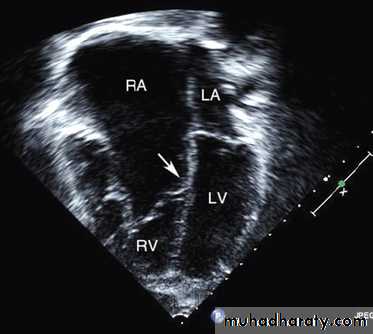

Ebstein anomaly consists of downward displacement of an abnormal tricuspid valve into the right ventricle.Pathophysiology

The right ventricle is divided into 2 parts by the abnormal tricuspid valve: the 1st, a thin-walled “atrialized” portion, is continuous with the cavity of the right atrium; the 2nd, often smaller portion consists of normal ventricular myocardium.

RV output is decreased due to a combination of the poorly

functioning small right ventricle and tricuspid valve regurgitation,

Echo is diagnostic and shows the abnormalities.